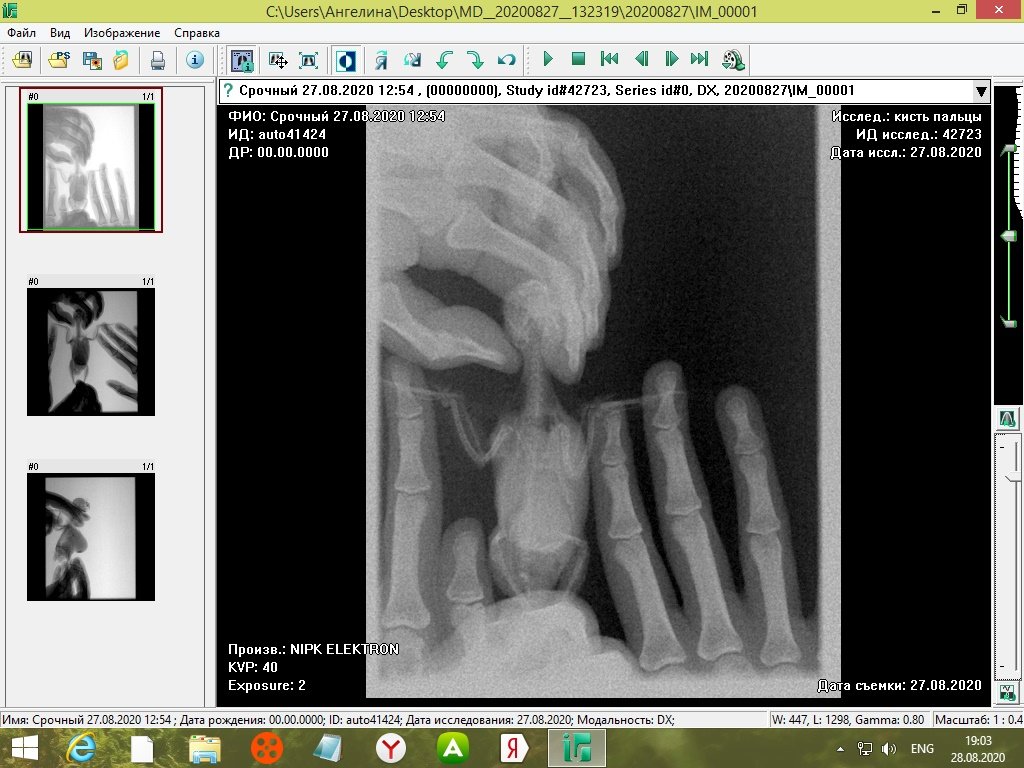

tanushka-sol2020 Опубликовано 27 августа, 2020 Автор #15 Опубликовано 27 августа, 2020 Некадрированные исходные снимки --- щёлкните полосу ниже. Скрытый текст

Кузяныч Опубликовано 28 августа, 2020 #16 Опубликовано 28 августа, 2020 Ох, бедная волнушка... В помёте на шли бактерии (++), слизь (+), жир (+), клетчатку (++)... Есть и непонятные для меня записи... По рентгену на втором снимке справа мне видится что эта огромная припухлость --- растянутый зоб... 18.08.2020 в 17:16, tanushka-sol2020 сказал: Что за опухоль? Она в моих руках меняется: то сморщится, то раздувается как шар надувной... Неужели, действительно зоб?... @tanushka-sol2020, срочно звоните Зосе, просите посмотреть снимки. Мазок из клюва... уф-ф... не знаю пока на сколько он нужен... Если на нистатине птице легче, то давайте его --- придерживайтесь дозировок, что давала вам Зося. Расположите лесенку горизонтально чтоб попугайчик экономил силы. Установите всё как можно ниже к полу. Проверьте, чтоб птичка не пыталась лезть выше и не висла на стенке. Помёт оранжевый... возможно, действительно, печень страдает... Карсил не отменяйте... За гепатовет и как вообще быть я не могу сказать. Нужно чтоб Зося посмотрела рентген. Свяжитесь, пожалуйста, с ней. У меня такое впечатление, что у этой волнушки растянут зоб и от этого плохо уходит и застаивается, протухая, пища.

tanushka-sol2020 Опубликовано 28 августа, 2020 Автор #17 Опубликовано 28 августа, 2020 (изменено) @Кузяныч К сожалению, от нистатина у нее сильно страдает печень. Я не стала ей давать, почти 3 недели принимали. Но срыгивание снова вернулось. Когда я собирала мазок из глотки, она потом срыгнула на одежду. Капли были песочного цвета и консистенция, как каша жиденькая. Но с запахом. Переживаю, вдруг неправильно сделала мазок, впервые же. Во вторнике будет готов анализ. Отпишусь. Рентген делали в больнице, я их кое-как уговорила. Первый "блин с комом", тоже выложила. Вдруг качества нет на снимке, что показал. Завтра Зосе позвоню. Спасибо, что ответили. Эти снимки неудачные выше, племянница скидывала. Я немного контраст отрегулировала, чтобы было видно. Изменено 28 августа, 2020 пользователем tanushka-sol2020